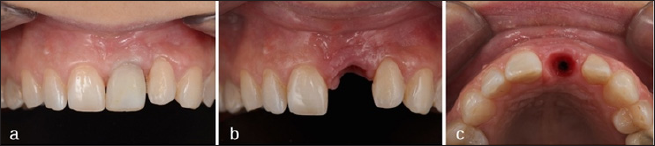

After 6 months healing impressions were taken to confection a diagnostic wax-up, and then a radiological splint. After the CBCT Scan, implant planning was performed with MGuide® Software (MIS Implants Technologies, Israel) (Figure 3). Under local anesthesia a 4 per 10 mm. Astra TX® implant (Astra Tech®, Densply, Sweden) was placed, due to the poor availability of bone an implant dehiscence was created in the buccal area, simultaneous bone regeneration was performed with Xenograft (Bio-Oss®, Geistlich Biomaterials, Parma, USA) and membrane (Mem-Lok®, Bihorizons, Birmingham, USA) [7]. As high implant primary stability was not achieved patient continued with the Maryland Bridge during the healing period (Figure 4). Six months after implant placement, a connective tissue graft harvested from tuberosity was performed to improve soft tissue contour around implant. An atraumatic second surgery [8] was performed using the provisional Maryland Bridge that the patient wears during healing period by the progressive addition of filling material.

Figure 6: Soft Tissue Management: (a) Frontal View with Implant-Screw Provisional Restoration; (b) Frontal View if the Emergence Profile; (c) Occlusal View of the Emergence Profile.